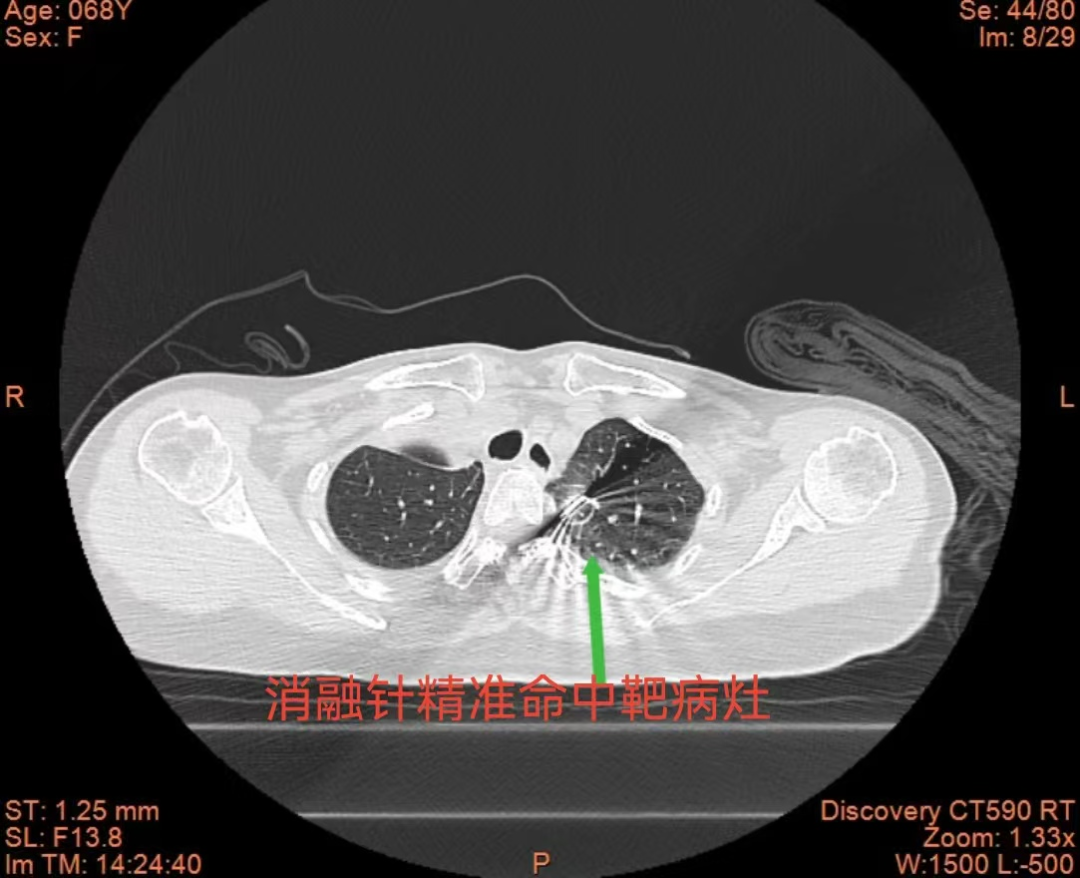

术中,团队在CT精准导航下,先向左侧胸腔缓慢注入空气,构建人工气胸,在左上肺结节与主动脉弓之间形成安全空气隔离带,同时配合液体隔离技术,有效减轻术中疼痛。凭借精准的穿刺技巧与术中的严密监测,消融针精准抵达病灶,手术顺利完成,目前患者已康复出院。

此次手术的成功,是我院呼吸介入团队精准医疗、微创创新的生动实践。人工气胸及液体隔离辅助下的微波消融术,既解决了高危部位结节“不敢做、做不好”的痛点,又能减轻患者疼痛、提高舒适感。